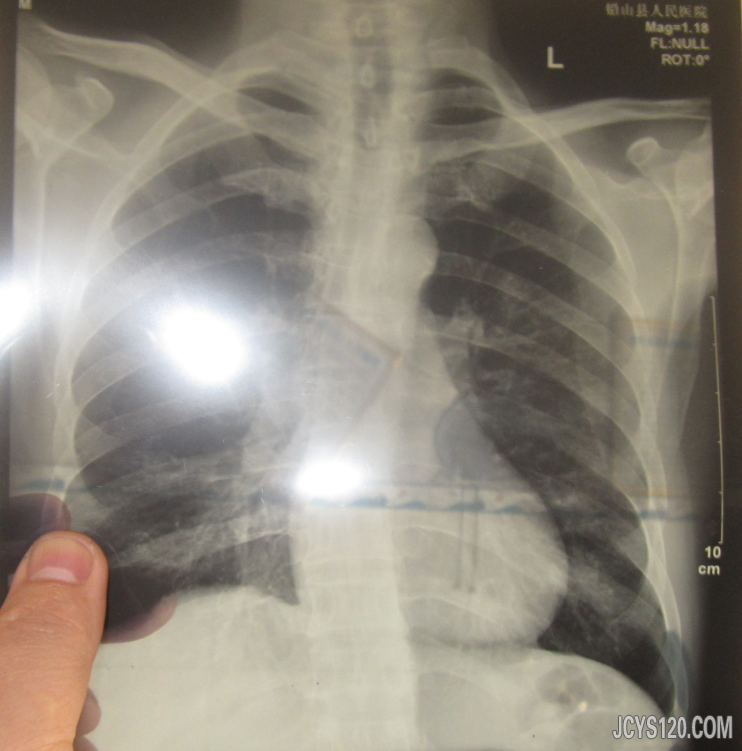

现在回想起来,自己当时是诊断有问题的。 如果是脑出血,为什么不是偏瘫,并且肌张力会没有?也就是软瘫吧。按理中枢性瘫痪肌张力是亢进的。脑出血都到昏迷了,为什么瞳孔等大,对光反射存在。这些都是指向推翻我诊断的。

综上述,此患者昏迷很可能是癔病或癫痫,而住院的检查只不过是合并症。